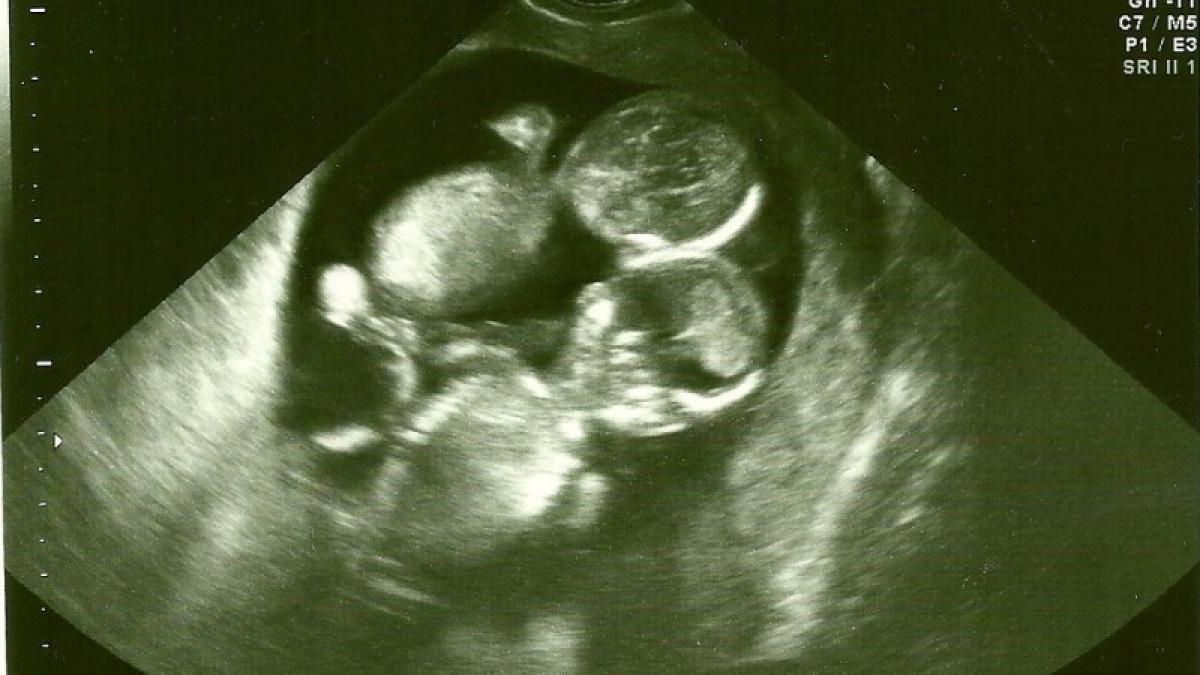

A mers la spital pentru prima ecografie. Când medicul a văzut imaginea a înghețat, a trimis-o acasă și i-a spus să se roage la Cel de Sus. Ce s-a întâmplat la naștere 26 Mai